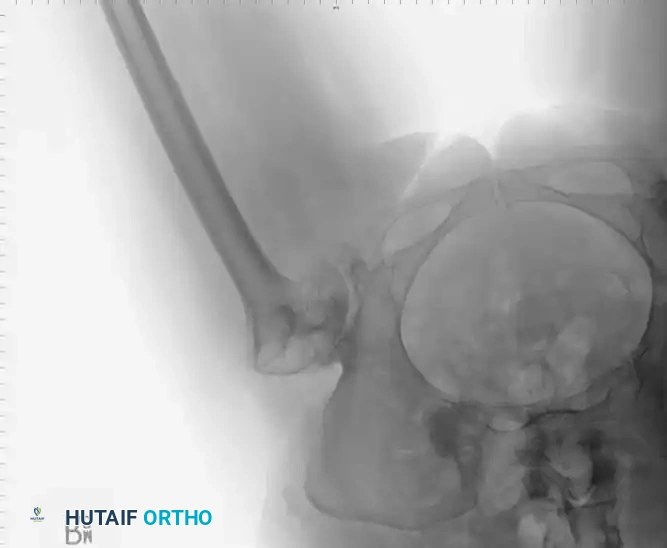

Radiographic Case Examples: Osteonecrosis and Complex Femoral Reconstructions

Advanced osteonecrosis with subchondral collapse and secondary arthritis.

Intraoperative imaging showing retained fibular graft from a previous joint-preserving procedure.

Use of a high-speed burr to clear the intramedullary canal of sclerotic graft remnants.

Fluoroscopic confirmation of proper broach alignment after graft removal.

Final seating of a cementless femoral stem in optimal neutral alignment.

Postoperative radiograph confirming excellent fit and fill of the femoral component.